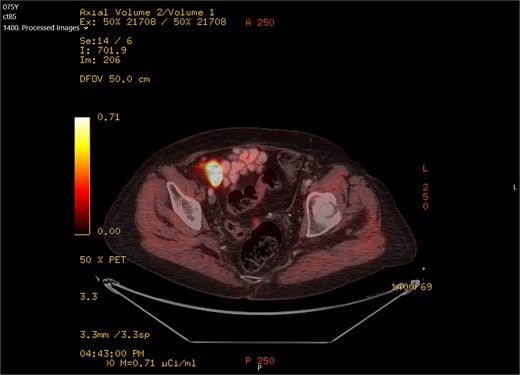

A 75-year-old woman with a past surgical history of serous papillary ovarian carcinoma underwent complete debulking surgery and adjuvant chemotherapy treatment 2 years prior to her current presentation. During follow-up, increased FDG uptake along with a 1.2-cm mass was seen on a PET-CT on the serosal surface of the recto-sigmoid junction (Fig. 1). An attempt was made to evaluate the lesion using trans-rectal sonography. Radial sonographic view showed a 12 mm, hypoechoic, well-defined lesion located at the serosal surface of the recto-sigmoid junction (Fig. 2). After reverting to a linear view, the lesion was sampled with fine-needle biopsy (Fig. 3) and whitish thick cores were retrieved (Fig. 4). The procedure was uneventful and no adverse events were noted. Pathology revealed fragments of high grade serous carcinoma of tubo-ovarian origin. Relying on the histological information gained from the biopsy, it was known that the lesion although not obvious to the eye during surgery, had to be found and resected. The surgical procedure was challenging with multiple adhesions, which made it difficult to locate the lesion. Based on the valuable preoperative knowledge, the patient was able to have a complete debulking of the tumor mass.

PET-CT scan showing FDG uptake at the recto-sigma junction seen as small bright spot in the middle of the screen.